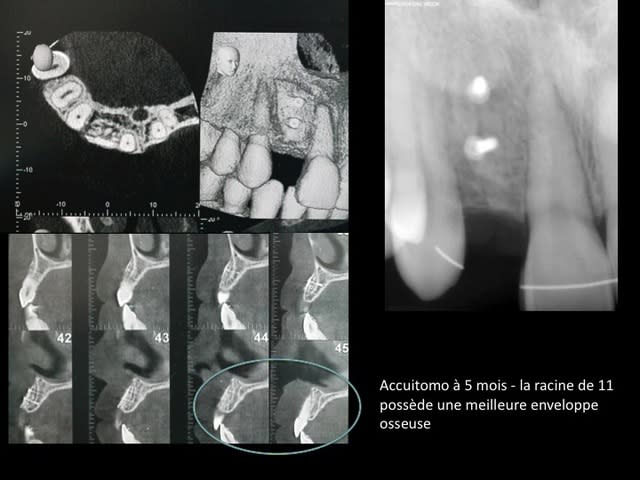

la suite et le début:

scan pré op: pas bcp d'os dispo au niveau de 46 47, y'a fallu aller plus loin derrière

la 11: voir son axe et le peu d'os autour en vestibulaire

photo de la cica à quelque mois

bientôt scan et pose de l'implant